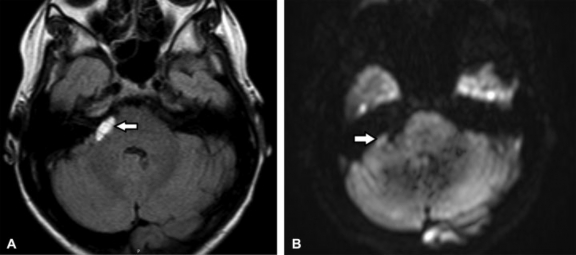

Tienen origen ectodérmico localizándose en la línea media en las cisternas de la fosa posterior.3,4,5,8 Se visualizan en TC como masas hipoatenuadas bien definidas debido a su contenido graso.3 En RM se observan hiperintensos en ponderación T1 y FLAIR, heterogéneos en ponderación T2 debido a su contenido rico en: colesterol, queratina, glándulas sebáceas, folículos pilosos, células descamadas, dientes y debris (►Fig. 16).3,4,5,8 En secuencias ponderadas con supresión grasa presentan atenuación irregular.4,5,8 En caso de ruptura de quiste, el diagnóstico se realiza observando gotas grasas en las cisternas, espacio subaracnoideo, cavidades ventriculares o surcos.5 Suelen no realzar y restringen en la secuencia difusión.16,17 Entre los diagnósticos diferenciales se mencionan:3,4,8

(A-B) RM de cerebro. Cortes axial en ponderación T2 (A) y sagital STIR T2 (B). En la fosa posterior, localizado en la línea media se visualiza una imagen de apariencia quística con contenido heterogéneo (flecha). En la secuencia con supresión grasa presenta atenuación heterogénea (*). Dado su comportamiento en imágenes así como su localización es compatible con quiste dermoide.